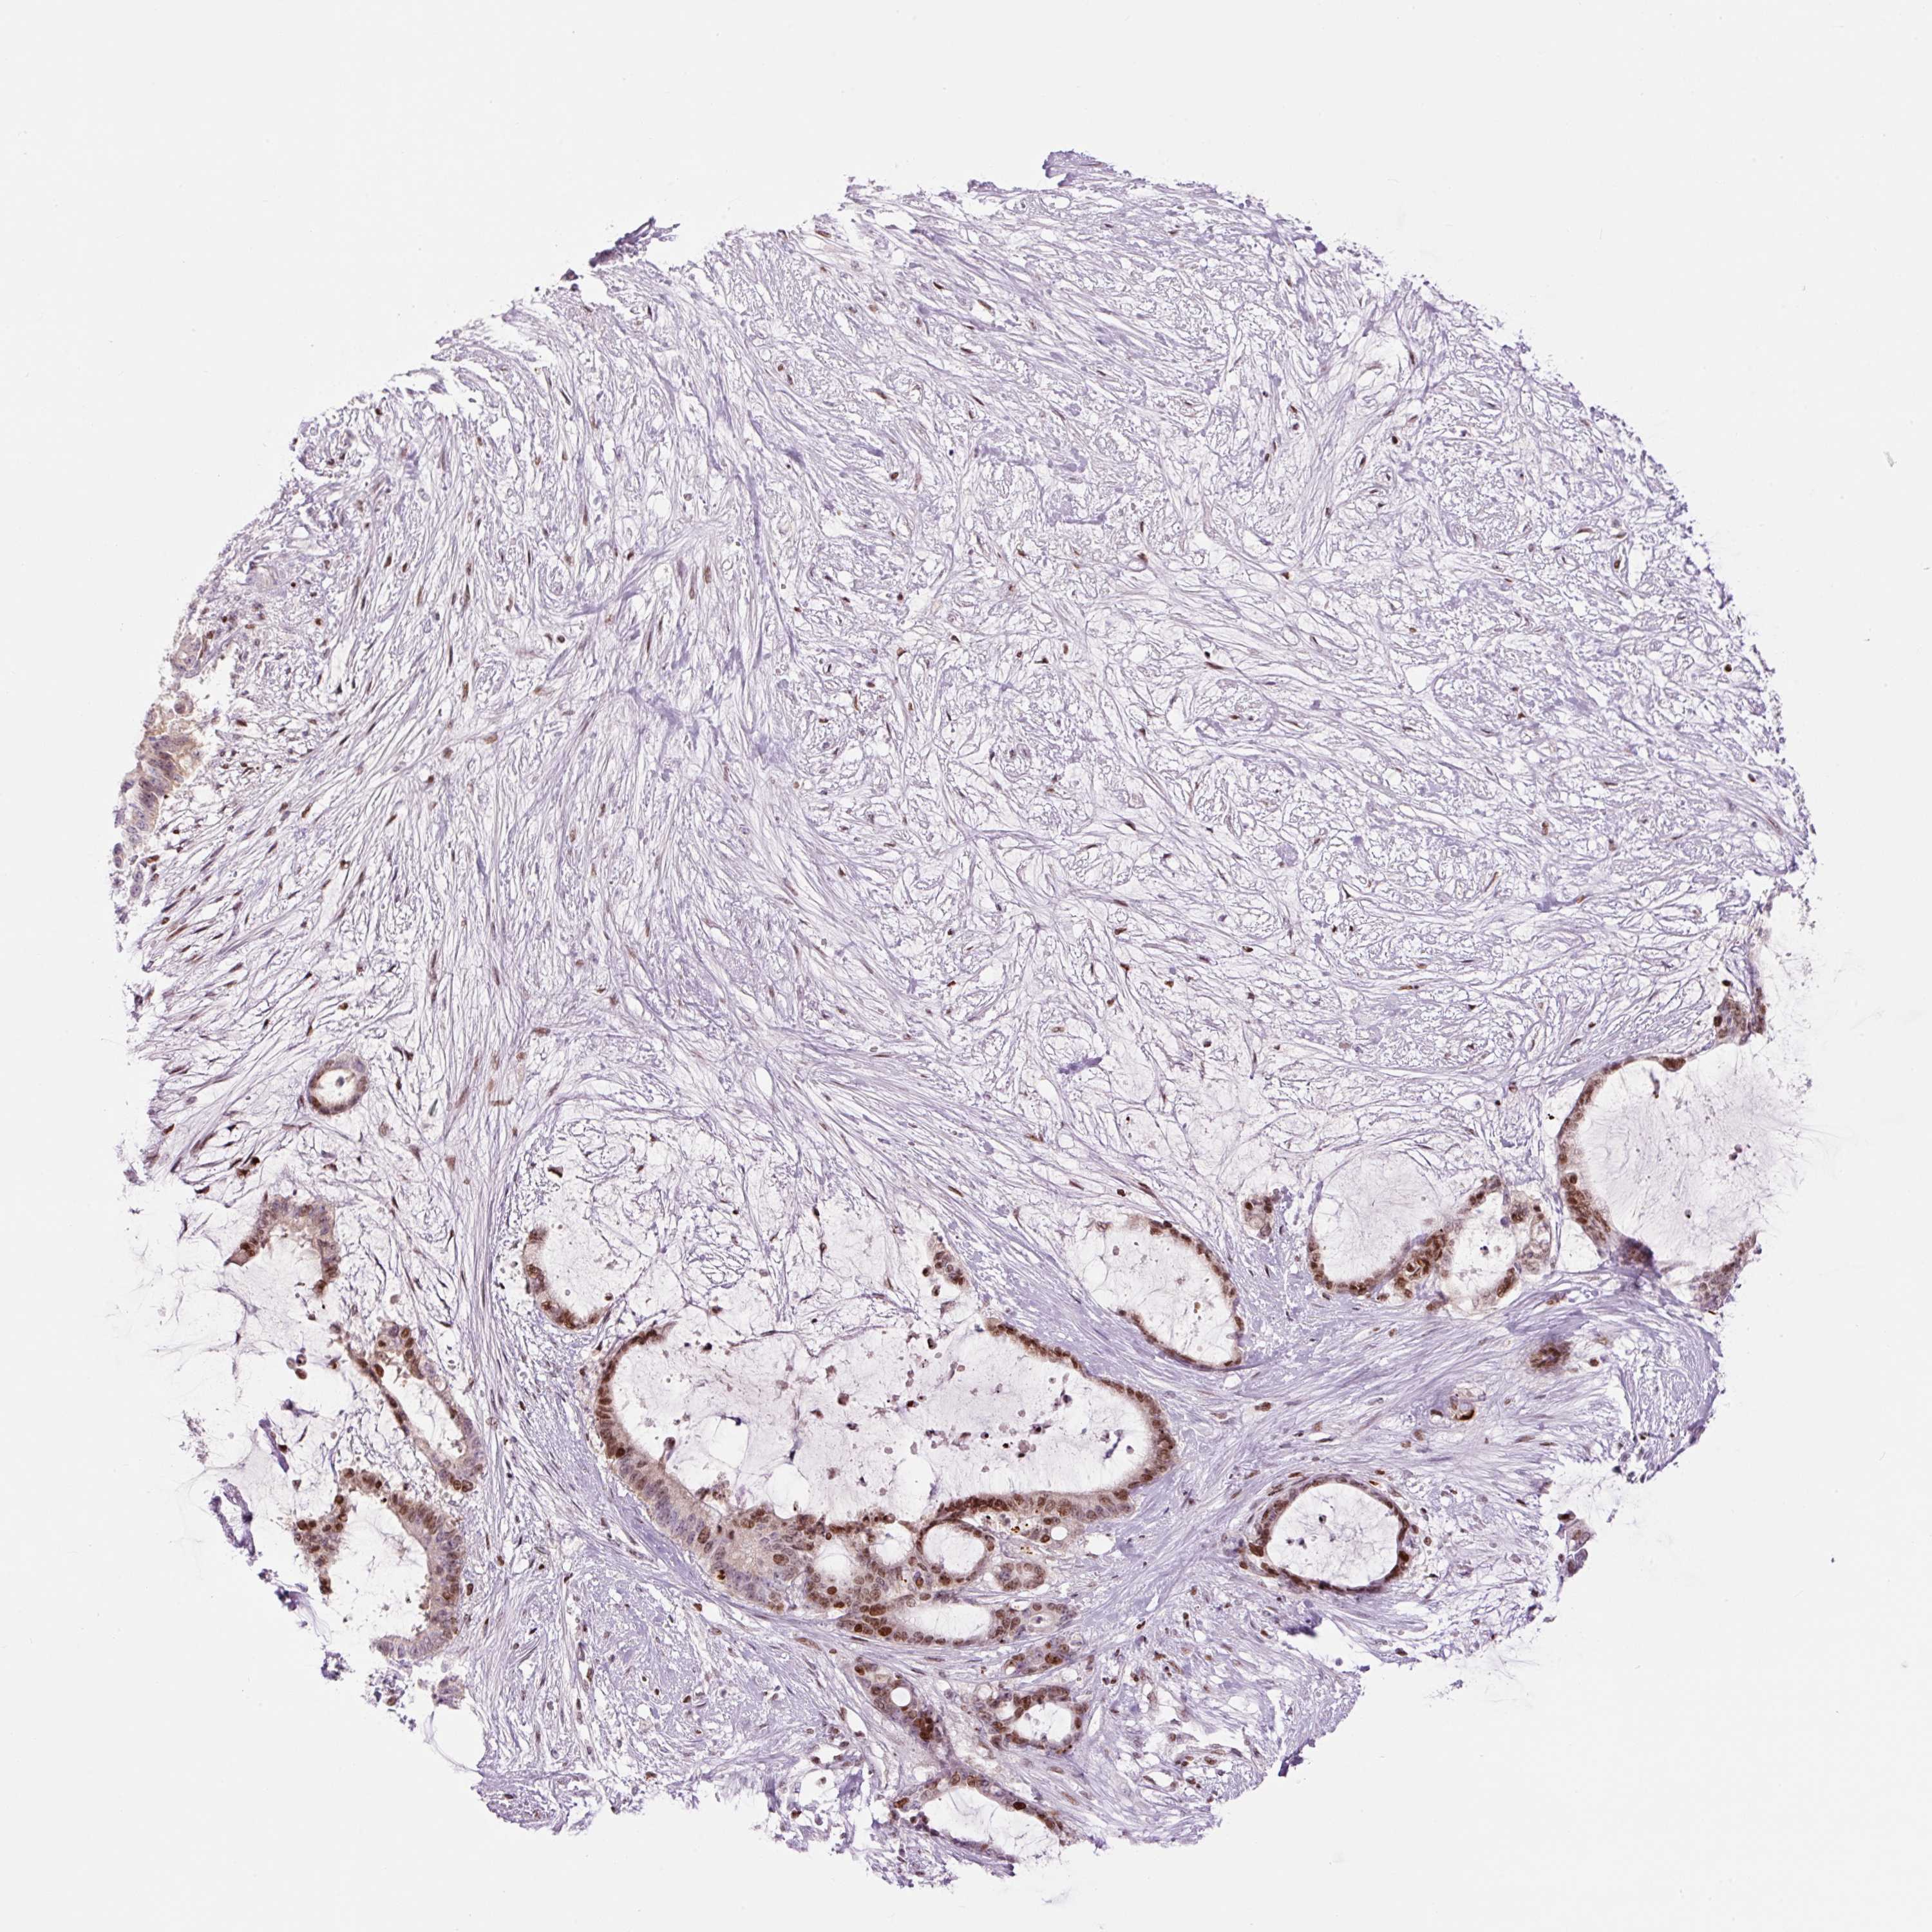

LIVER CANCER - Protein expressioni

A mouse-over function shows sample information and annotation data. Click on an image to view it in a full screen mode. Samples can be filtered based on level of antibody staining by selecting one or several of the following categories: high, medium, low and not detected. The assay and annotation is described here.

Note that samples used for immunohistochemistry by the Human Protein Atlas do not correspond to samples in the TCGA dataset.

Antibody stainingi

Antibody staining in the annotated cell types in the current human tissue is reported as not detected, low, medium, or high, based on conventional immunohistochemistry profiling in selected tissues. This score is based on the combination of the staining intensity and fraction of stained cells.

Each image is clickable and will lead to virtual microscopy that enables deeper exploration of all samples and also displays staining intensity scores, fraction scores and subcellular localization as well as patient and tissue information for each sample.

Antibody HPA053816

Staining

High

Medium

Low

Not detected

Intensity

Strong

Moderate

Weak

Negative

Quantity

>75%

75%-25%

<25%

None

Location

Nuclear

Cytoplasmic/membranous

Cytoplasmic/membranous,nuclear

Carcinoma, Hepatocellular, NOS

Cholangiocarcinoma